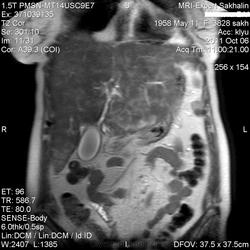

Постконтраст.

Добавила постконтраст.

Так все же, что здесь? Метастазы?

Предложу еще варианты:

Туберкулез

Лейкоз

Саркоидоз

Направили на консультацию  к гематологу и онкологу.

Склоняюсь к мета, при саркоидозе сходной картины не видел, очаги совсем другие.